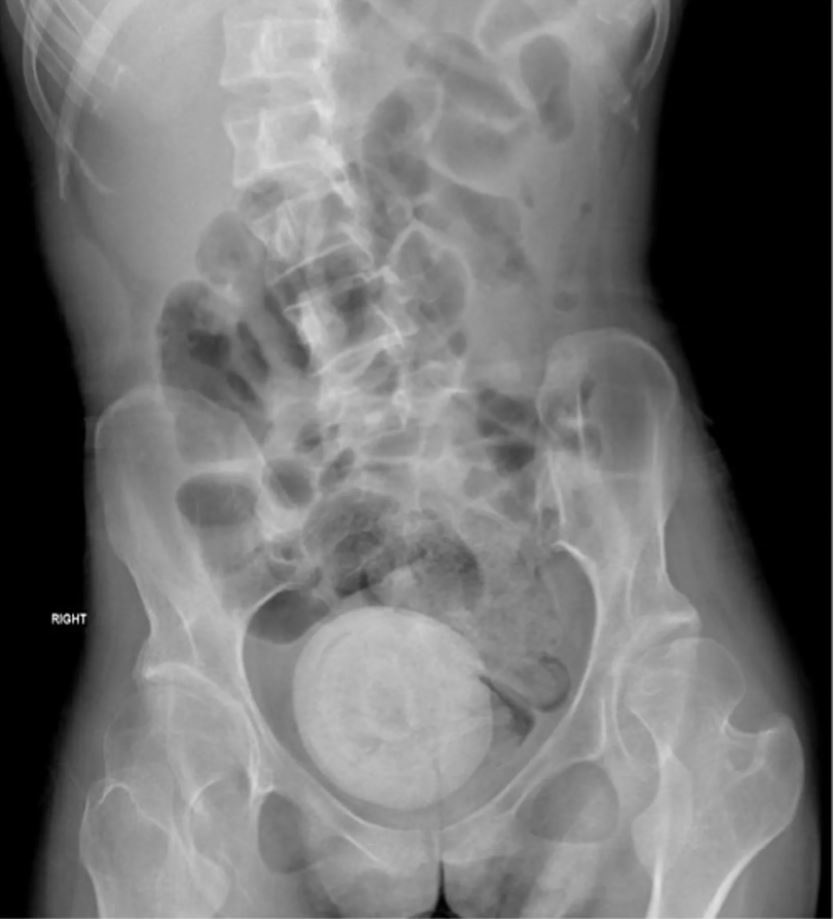

Η αξονική τομογραφία της λεκάνης και της κοιλιάς αποκάλυψε τον “ένοχο”. Οι κολπικές πέτρες «σχηματίζονται από την εναπόθεση ανόργανων αλάτων από στάσιμα ούρα μέσα στον κόλπο», σύμφωνα με μια ερευνητική εργασία του 2019 που δημοσιεύτηκε στο Medicine . Λόγω της σπανιότητας της πάθησης, είπαν οι ερευνητές, έχει γίνει συχνά λανθασμένη διάγνωση στο παρελθόν.

Ο σχηματισμός ήταν τόσο μεγάλος που πίεζε την κύστη της γυναίκας, κάτι που οδήγησε σε ακόμη μεγαλύτερη διαρροή ούρων.